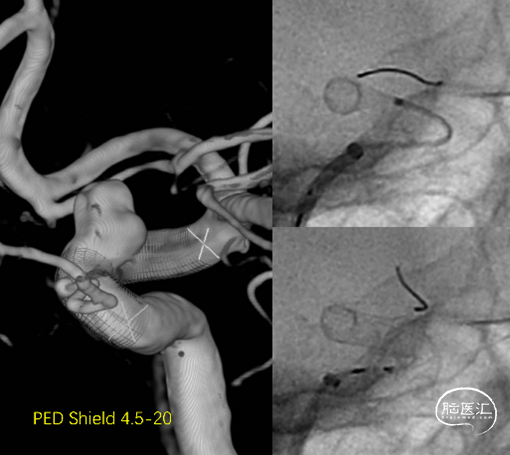

术后6月随访,可见动脉瘤愈合,载瘤动脉通畅(图5)。予以停用氯吡格雷。

图.5